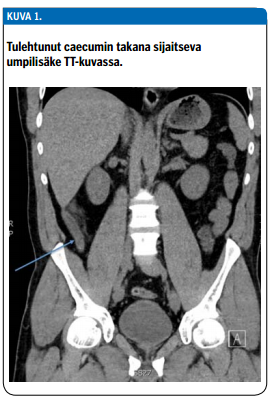

Tietokonetomografian tarkkuus ja herkkyys ovat selvästi paremmat kuin kaikukuvauksen tai kliinisen arvion. Sitä voidaan pitää perustutkimuksena silloin, kun potilaalla epäillään umpilisäketulehdusta mutta taudinkuva on jollain tavalla epätyypillinen. Umpilisäketulehduksen diagnostiikassa saadaan riittävä tarkkuus myös tavanomaista pienempiä sädeannoksia käytettäessä (14). Tutkimuksessa nähdään tavanomaista paksumpi umpilisäke ja ympäröivän rasvan turvotus (kuva 1 «»2). Tutkimuksissa TT-kuvauksen sensitiivisyys on ollut 91 % ja spesifisyys 90 %, mutta joissakin tutkimuksissa on päästy jopa 95 %:n spesifisyyteen. (15) Umpilisäkkeen kuoliota tai puhkeamaa ei voida TT-tutkimuksen perusteella luotettavasti todeta, mutta umpilisäkkeen viereinen paise näkyy kyllä (16,17).